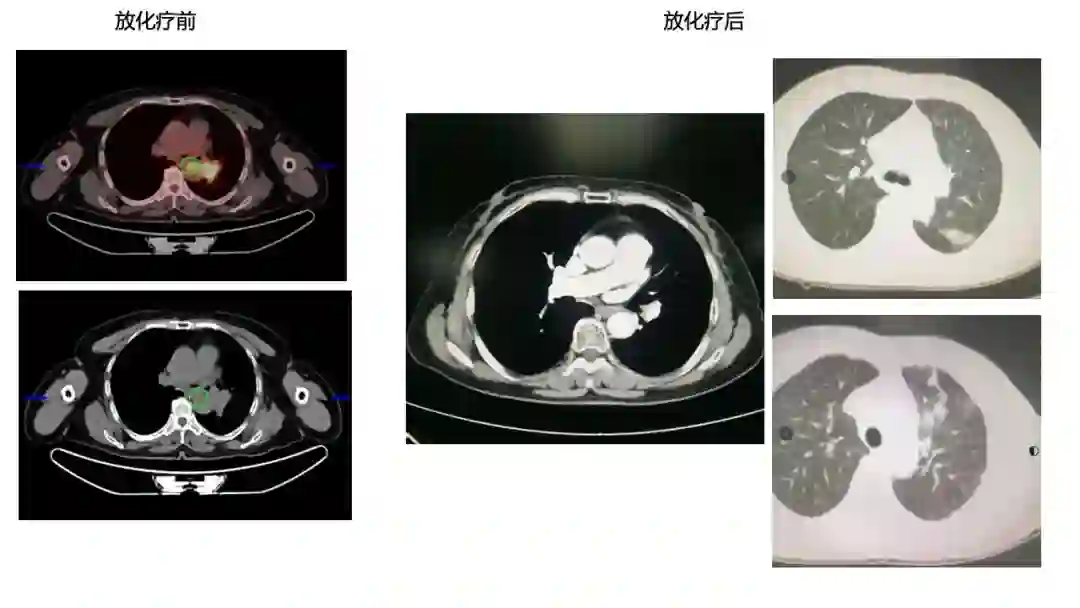

2)患者2017年11月因晨起咯血丝痰在外院行CT提示肺部肿物,考虑肺癌,后于2017-11-20我院行PET-CT,提示左肺下叶肿块,纵隔8L组淋巴结肿大,糖代谢增高,考虑左肺下叶中央型肺癌并纵隔淋巴结转移;左肺下叶阻塞性炎症。

2018-01-11开始行同步放化疗,放疗予以IMRT 60Gy/30F,化疗予以EP方案同步2周期。

图表资料

3)原发灶+8组LN(放疗区) PR 疗效。